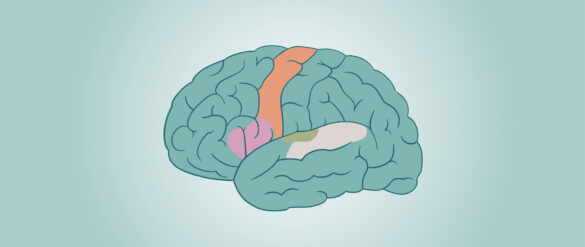

¿Cuáles son las áreas de asociación en el cerebro?

Aunque es bien conocido que la corteza cerebral está dividida en múltiples áreas, a menudo se pasa por alto que una gran parte de su superficie está ocupada por las áreas de asociación. Estas regiones desempeñan un papel crucial al procesar información compleja, integrando los…